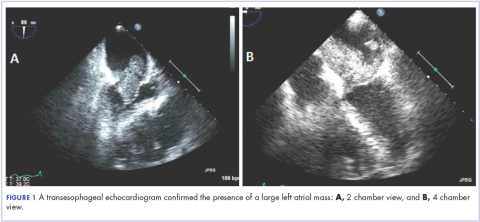

A 56-year-old woman with history of left atrial myxoma status after resection in 2005 and placement of a Dacron graft, morbid obesity, hypertension, and asthma presented to the emergency department with progressively worsening shortness of breath and blurry vision over period of 2 months. Acute coronary syndrome was ruled out by electrocardiogram and serial biomarkers. A computed-tomography angiogram was pursued because of her history of left atrial myxoma, and the results suggested the presence of a left atrial tumor. She underwent a transesophageal echocardiogram, which confirmed the presence of a large left atrial mass that likely was attached to the interatrial septum prolapsing across the mitral valve and was suggestive for recurrent left atrial myxoma (Figure 1). The results of a cardiac catheterization showed normal coronaries.